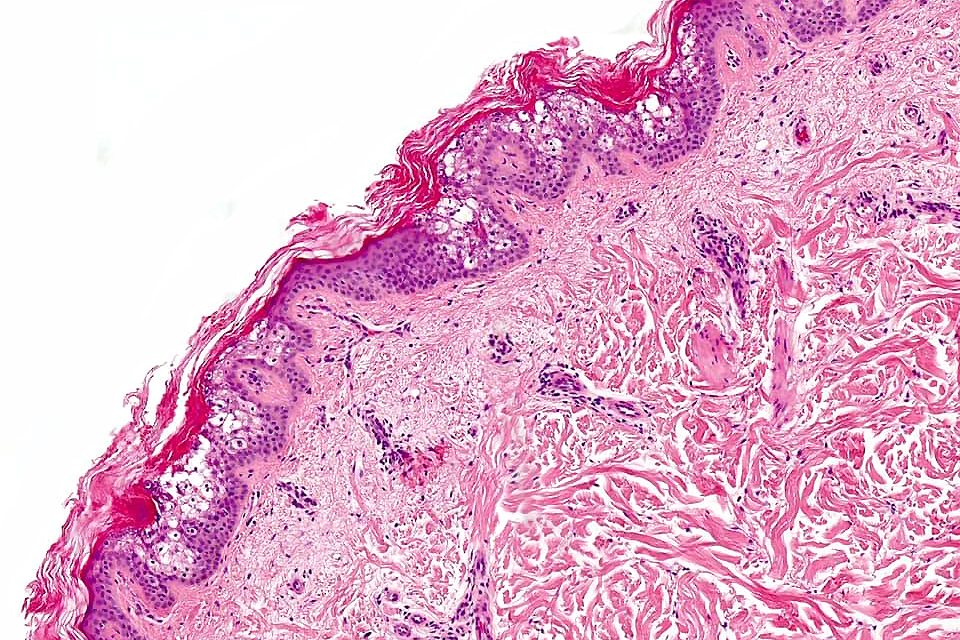

•Cup-shaped circumscribed lesion showing hyperkeratosis, focal parakeratosis & acanthosis

•Superficial epidermis shows often multifocal keratinocyte vacuolation with eosinophilic cytoplasmic inclusions & sometimes epidermal necrosis